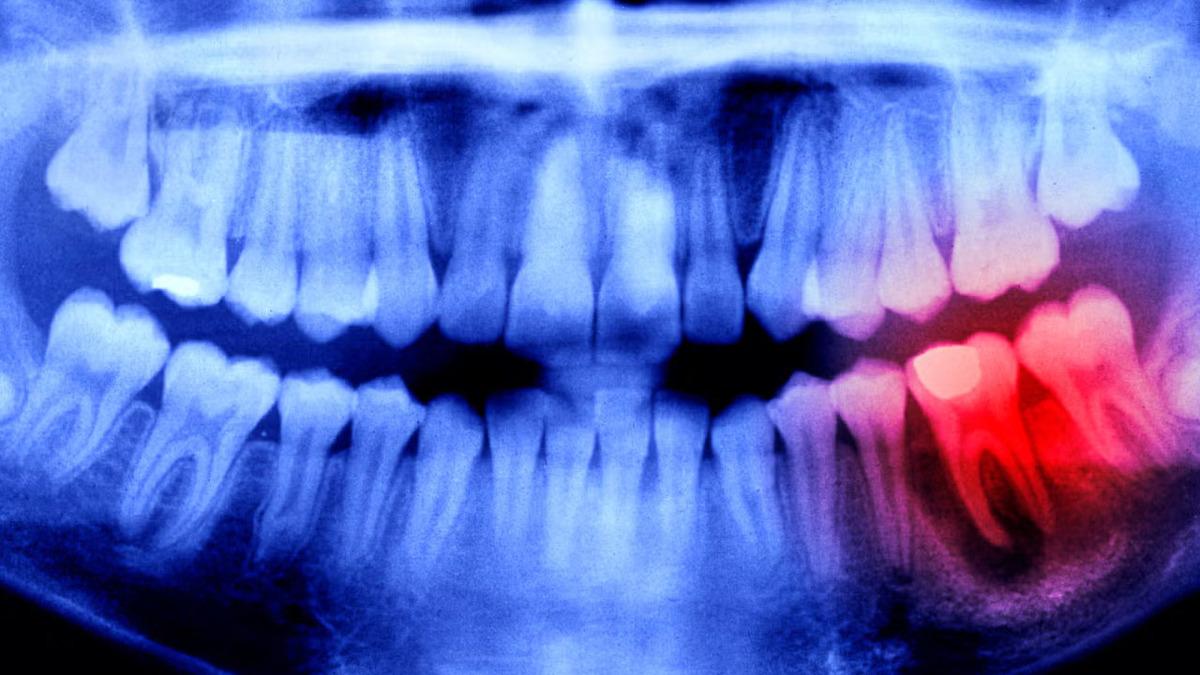

Dişler, yapıları gereğince kemiklerle aynıdırlar. Ancak kemiklerin aksine dişlerin kendini yenileme, kırılma hâlinde onarım gibi bir özellikleri yoktur. İşte Japon bilim insanları, geçmişten gelen bilgi birikimini de kullanarak bu duruma bir çözüm ürettiler. Bilim insanları, 2030 yılı itibarıyla ilacı genel kullanıma açacaklarına inanıyorlar.